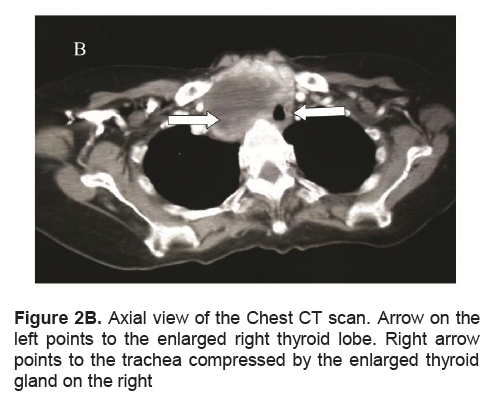

A frail, 71-year-old female in mild respiratory distress presented at the Emergency Room. Her condition started 2 weeks prior to consult she started to experience shortness of breath and easy fatigability. Pertinent in the history was a goiter which was untreated for several years. There was no noticeable rapid enlargement of the thyroid gland, but there was hoarseness for the past 15 years. She noted weight loss in the last 8 months. She had no prior history of neck radiation, nor family history of goiter. Palpitations and easy fatigability were also present. At the time dyspnea became progressive, patient became weak, and appetite started to decrease. Physical examination showed she was tachycardic, tachypneic, febrile with wheezing and crackles on both lung fields. No palpable thyroid nodules and no cervical lympadenopathy were appreciated. Initial impression was pneumonia with marked leukocytosis at 22.70mg/dl with toxic granules. Chest x-ray showed pulmonary nodules and right superior mediastinal mass, inflammatory versus neoplastic in origin. Thyroid function test results showed suppressed TSH 0.01uIU/mL (normal 0.35-4.94uIU/mL), FT3 6.37pg/mL (normal 1.45-3.48), and elevated FT4 2.36 ng/dL (normal 0.71-1.85). Patient underwent thyroid scan which showed non-hyperactive multinodular goiter with cold nodules dominant on the right and focal hot areas in both lobes suggestive of goitrous thyroiditis (Figures 1A, 1B, 1C). Thyrotropin receptor antibodies were negative. Ultrasound of the thyroid revealed bilateral thyroid nodules. The right lobe showed three solid nodules with the following measurements: 2.1 x 1.8 x 1.10 cm (with peripheral vascularity), 3.7 x 3.3 x 2.0 cm, and 5.0 x 3.7cm (with calcifications and minimal internal and peripheral vascularity). Left lower thyroid lobe had complex nodules with the following measurements: 2.0 x 2.4 x 1.8 cm (predominantly solid) and 4.2 x 3.3 x 2.4 cm (with peripheral vascularity). Treatment for her thyrotoxicosis was started with propylthiouracil 50mg/tab 4 tabs every 8 hours. With persistent shortness of breath, a chest CT scan with intravenous contrast was done and it showed several mildly enhancing, well circumscribed pulmonary nodules in both lung fields. The largest nodule measured 1.5cm in its widest diameter, while most of the nodules were subcentimeter in diameter. The enlarged right thyroid lobe spanned an approximate length of 9cm and extended into the superior mediastinum. (Figure 2A). The mass compresses the mid segment of the trachea to the left, narrowing its lumen (Figure 2B). After several days of treatment with antibiotics and anti-thyroid medications, the patient had improved and dyspnea had markedly lessened.

Figure 2B. Axial view of the Chest CT scan. Arrow on the left points to the enlarged right thyroid lobe. Right arrow points to the trachea compressed by the enlarged thyroid gland on the right